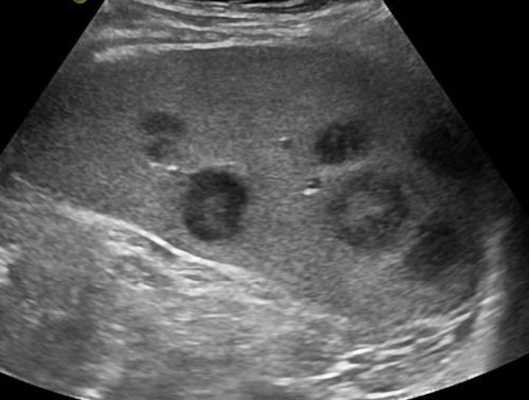

Увеличение лимфатических узлов при лимфогранулематозе

УЗИ с допплерографией у пациентов онкологического профиля показывает следующие нарушения в строении ЛУ:

- увеличение в размерах - обычно до 6-6,5 см;

- шарообразную деформацию или неправильные контуры;

- спаянность в виде конгломератов;

- отсутствие дифференциации на кору и ворота;

- неоднородность структуры с зонами повышенной и пониженной эхогенности;

- жидкостные включения и кальцинаты;

- усиленный кровоток и образование новых сосудов (ангиогенез).

Указанные изменения на снимках чаще обнаруживают при лимфоме.